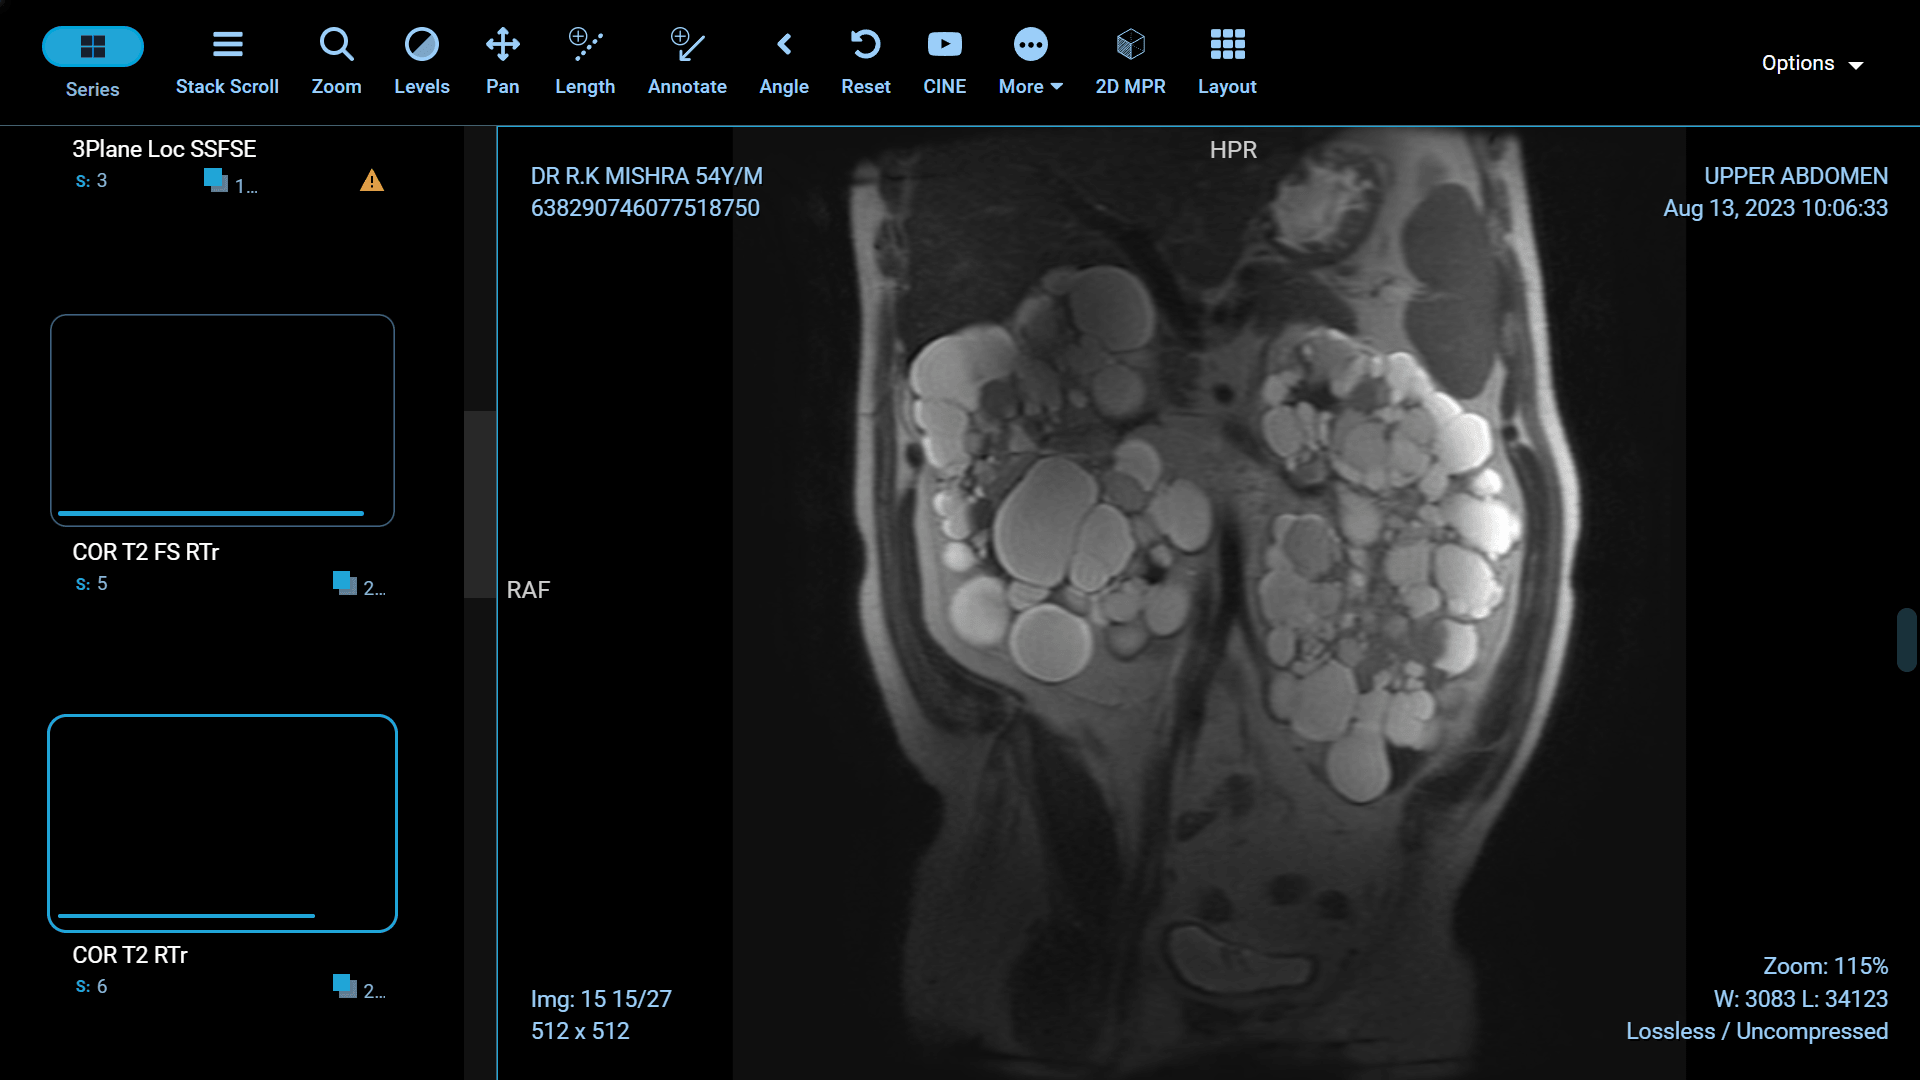

Polycystic Kidney Disease (PKD) is a genetic disorder characterized by the formation of fluid-filled cysts in the kidneys, which can lead to renal failure if left untreated. Fortunately, recent advancements in medical science have paved the way for more effective treatments and improved the quality of life for those affected by this condition. In this article, we will explore some of the groundbreaking innovations in PKD treatment.

Foam sclerotherapy is a medical procedure that involves injecting a specialized foam directly into kidney cysts. The foam is made by mixing a liquid sclerosing agent, typically a solution of alcohol or polidocanol, with air or gas to create a stable, persistent foam. This foam is then injected into the cyst through a thin needle under ultrasound or CT guidance.

The success of foam sclerotherapy lies in its ability to cause intentional injury to the cyst lining, promoting inflammation and scarring. This process leads to the collapse and sealing of the cyst, preventing further fluid accumulation and reducing the cyst's size.

Minimally Invasive: Foam sclerotherapy is a minimally invasive procedure, which means it typically requires only a small incision or needle puncture. This reduces the risk of infection, pain, and complications associated with more invasive surgical procedures.

Preservation of Healthy Kidney Tissue: Unlike some other treatments, foam sclerotherapy specifically targets the cyst, leaving the surrounding healthy kidney tissue intact. This is particularly important for individuals with only one functioning kidney.